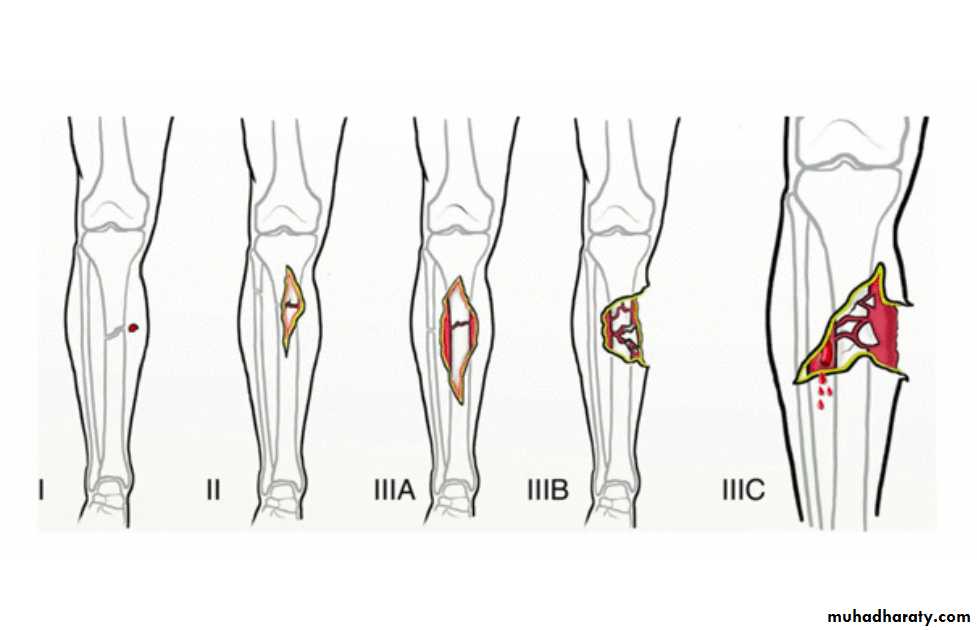

Open Fractures

A break in skin and underlying soft tissues leading directly to communicating with the fracture

Emergency Management of Open Fracture

fracture stabilization ( according to grade)